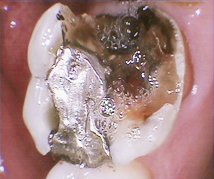

Large silver filling in premolar tooth. Silver filling replaced with a bonded tooth coloured filling.

Before

After